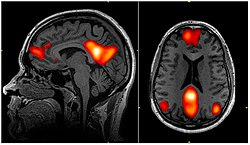

The Default Mode Network is best described as the brain state for when a person is not focused on external world, and instead brain it at wakeful rest. Think daydreaming and mind wandering. Primary brain structures involved are Medial Prefrontal Cortex, Posterior Cingulate Cortex, Precuneus, and Angular Gyrus.

In more technical terms, the Default Mode Network is a large-scale brain network that shows higher activity when an individual is at rest and not engaged in specific goal-directed tasks. It is associated with self-referential thinking, autobiographical memory, and envisioning the future. The network is thought to play a role in integrating internal and external information, as well as in social cognition.